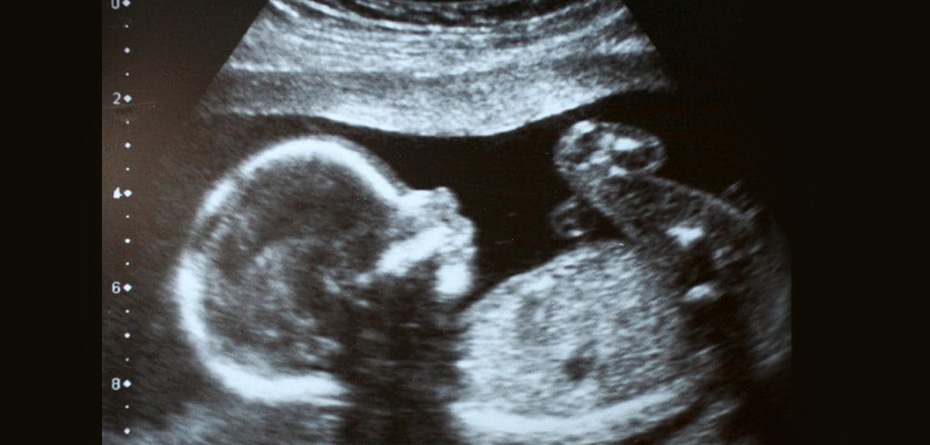

نوزاد باید به پشت دراز کشیده باشد تا این موضوع را ببیند. تصاویری که بلافاصله در زیر آورده شده اند از دو نوزادی هستند که در طول هفته ۱۳ ام بارداری هستند و برامدگی تناسلی را نشان میدهد.

نوزاد در سمت چپ یک آلت تناسلی دارد که در زاویهای است که بیشتر از ۳۰ درجه قرار دارد، پس احتمالاً یک پسر است. همچنین شبیه آلت تناسلی و کیسه بیضه نیز هست.

نوزاد در سمت راست یک آلت تناسلی دارد که بیشتر افقی است، موازی با ستون فقرات، بنابراین او احتمالاً دختر است. تفاوت میان دو بچه بالا کاملاً مشخص است، اما همیشه هم روشن نیست. در حقیقت، مطالعات نشان می دهند که این یک اتفاق زیبا و دلنشین است.